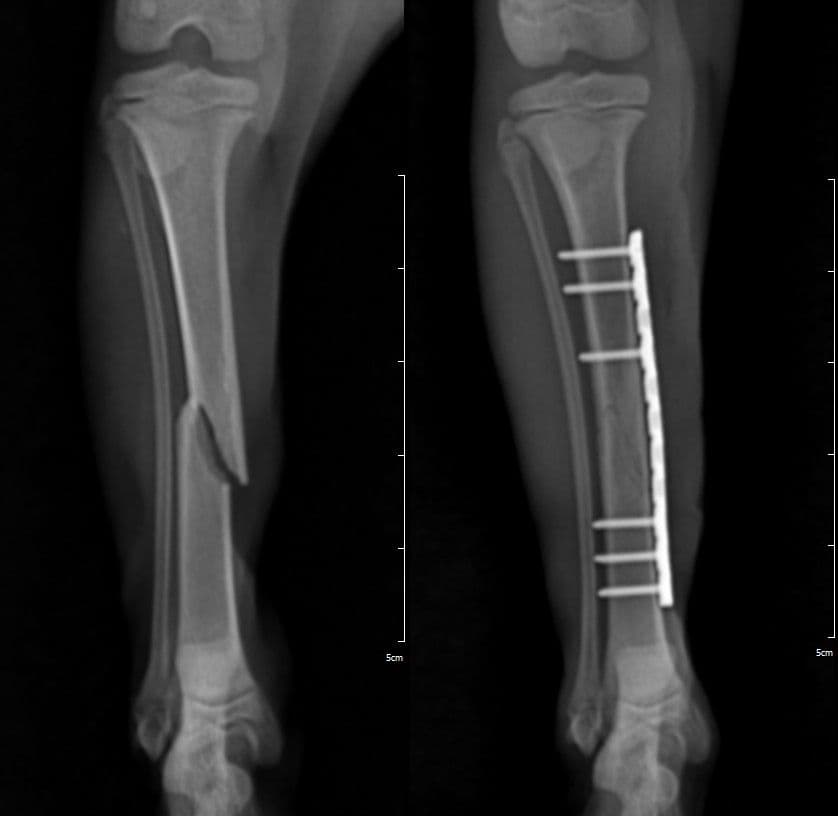

골절 수술

단순 골절, 복합 골절